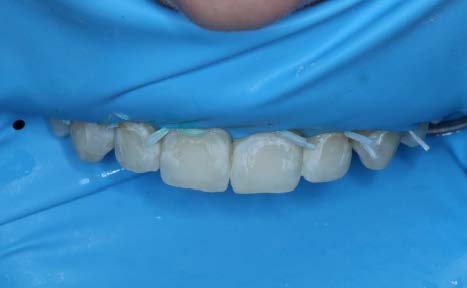

Intraoral exam revealed unesthetic white spot lesions on teeth #5 through #12. Tooth #10 also had small facial cavitation. The patient and mother were informed about the process of resin infiltration and that the outcome would likely improve the esthetic appearance, however, it could not be guaranteed. Also, the importance of using the rubber dam was explained to patient and the risk of HCl leakage through the rubber dam causing temporary blanching of tissue.

After allowing the Icon Dry to sit for 30 seconds and thoroughly drying the teeth, the resin Icon Infiltrant was applied for 3 minutes. The overhead light was removed and the resin was refreshed every minute. The excess resin was then blown away with an air-water tip and the teeth were flossed. Each tooth was then light cured for 40 seconds. A second round of infiltration was then applied, cured and a scaler was used to remove excess resin.

The patient and his mother were very pleased with the esthetic outcome. The patient had planned to return for a composite restoration for the cavitation on #10.